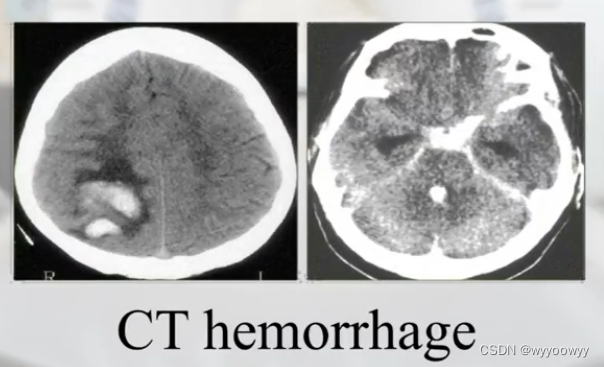

医学图像处理用的标准格式:.dicom

DICOM(Digital Imaging and Communications in Medicine)即医学数字成像和通信,是医学图像和相关信息的国际标准(ISO 12052)。它定义了质量能满足临床需要的可用于数据交换的医学图像格式。

8、医学图像的类别

三维扫描

核磁共振图片